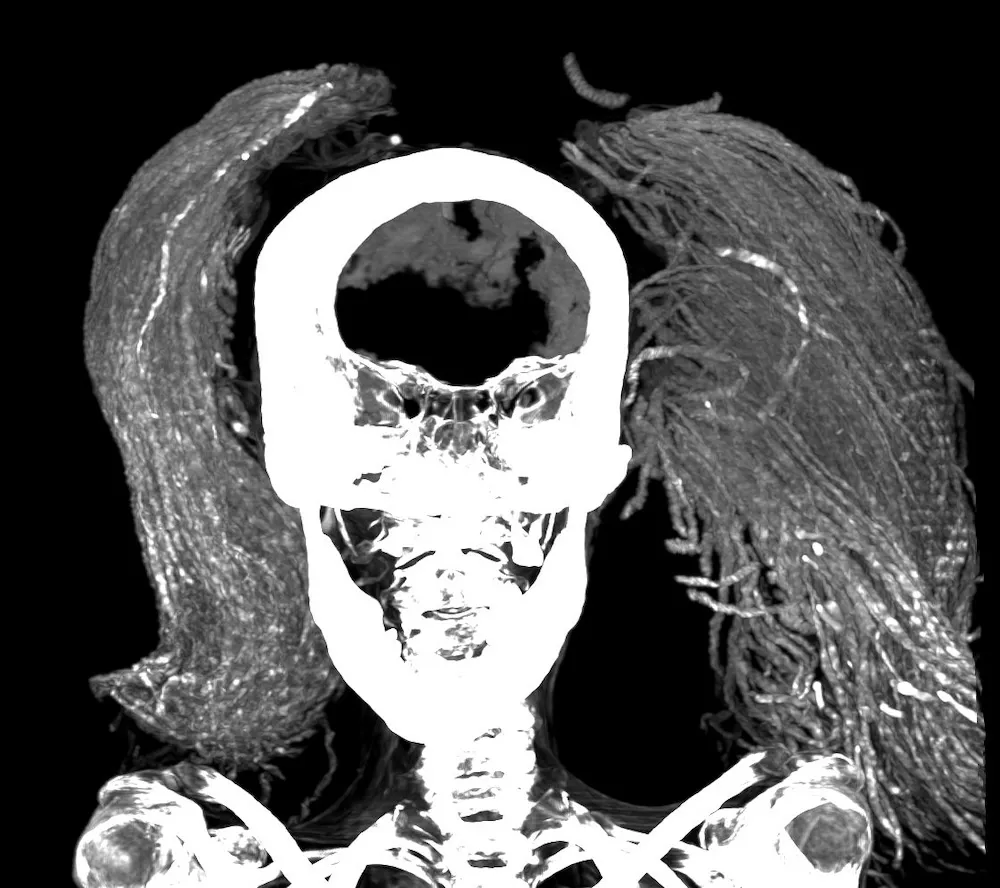

نشرت أستاذة الأشعة في مستشفى قصر العيني في جامعة القاهرة، سحر سليم، وزملاؤها دراسة جديدة في مجلة آفاق في الطب (Frontiers in Medicine) تقدم نظرة مفصّلة غير مسبوقة إلى هذه المومياء وفرضيات موثوقة حول حالتها الصحية قرابة نهاية حياتها. بفضل تقنيات التصوير المقطعي المحوسب والتحليل الطيفي بالأشعة تحت الحمراء والفحص بالمجهر الإلكتروني الماسح ومعدات أخرى، افترض فريق سليم أن الفم المفتوح قد لا يكون ناجماً عن عملية دفن رديئة الجودة، بل عن تشنج جثة المرأة في اللحظات الأخيرة من حياتها.

تشير المسوح إلى أن هذه المرأة التي بلغت من العمر نحو 48 عاماً افتقرت إلى العديد من أسنانها في وقت وفاتها، مع ذلك، تبيّن علامات ارتشاف العظام، وهي حالة تحدث عندما يلتئم تجويف السن الفارغ، إلى أنها فقدت هذه الأسنان في وقت سابق من حياتها. وفقاً لسليم، من المحتمل أيضاً أن متخصصاً ما قلع هذه الأسنان، علماً أن طب الأسنان نشأ في مصر القديمة. تشير الأدلة على وجود نتوءات عظمية في فقرات المرأة إلى أنها كانت مصابة بالتهاب طفيف في المفاصل النخاعية.

برز تفصيل مدهش فيما يتعلق بعملية تحنيط جسد المرأة الصارخة مميز عن أي تفصيل آخر، وهو غياب شق التحنيط. اعتقد علماء المصريات منذ زمن طويل أن التحنيط التقليدي في المملكة الحديثة (1550-1069 قبل الميلاد) ينطوي على إزالة أعضاء الجثة باستثناء القلب، لكن يبدو أن هذه الأعضاء كانت موجودة لدى المرأة الصارخة عندما جرى دفنها. بسبب ذلك، تفترض سليم أن ترك الأعضاء داخل الجسم ربما كان معتاداً في بعض الأحيان في ذلك الوقت.

أما بالنسبة لكيفية إعداد المرأة للتحنيط، فكشف تحليل تحويل فورييه الطيفي باستخدام الأشعة تحت الحمراء لجلد المومياء عن وجود العرعر واللبان، وهما من الكماليات التي استوردها المصريون من جنوب شبه الجزيرة العربية أو شرق إفريقيا أو شرق البحر الأبيض المتوسط. كان شعر المرأة الطبيعي مصبوغاً بالحناء والعرعر، لكنها كانت ترتدي أيضاً شعراً مستعاراً طويلاً مخصصاً للحياة الآخرة ومصنوعاً من أصابع نخيل التمر التي عالجها خبراء التحنيط ببلورات الألبيت والمغنتيت والكوارتز. استخدم المصريون القدماء هذه المواد غالباً لتقوية خصلات الشعر المستعار وجعلها تبدو سوداء اللون للإشارة إلى مظهر أكثر شباباً.